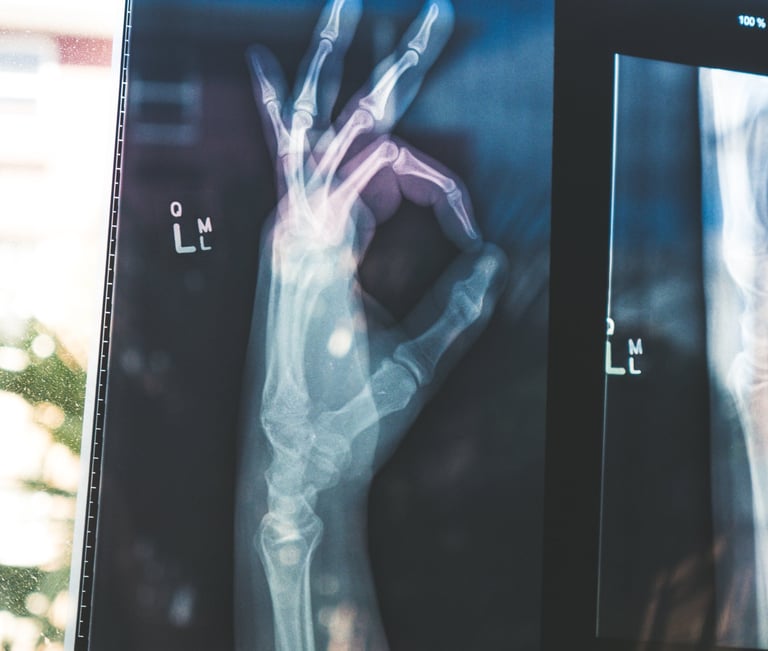

Photo by Wendy Scofield on Unsplash